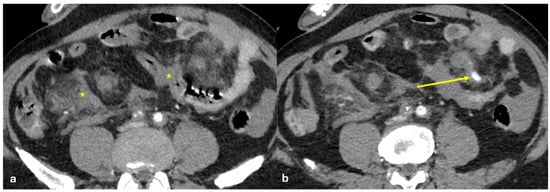

- Micro-nodular pattern: micro-nodules with a diameter ≤ 5 mm (Figure 1);

- Nodular pattern: nodules with a diameter > 5 mm (Figure 2a);

- “Omental cake”: nodular thickening of the omentum (Figure 2b);